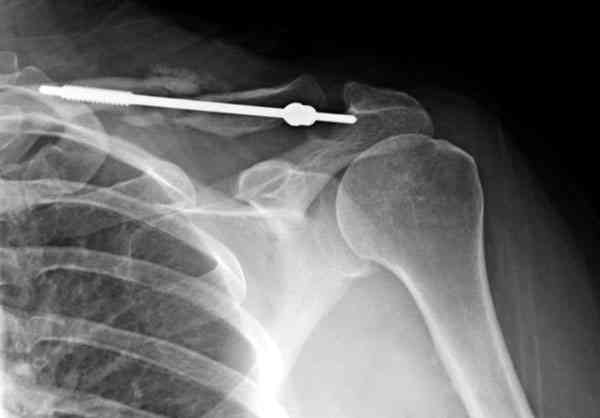

Консервативное лечение, через 8 мес. операция Rockwood pin с костной пластикой в нашем городе другим врачом. После 8 недели падение, гвоздь удален оперирующим хирургом, больная направлена к нам. Фиксация реконструктивной пластиной с трикортикальным графтом, добавлен BMP-2. Для стабилизации фиксацию провели через акромион.

Вот уже два месяца больная также продолжает жаловаться на боли, буквально на днях удалили акромиальную часть пластины с специальной пилой с алмазным покрытием для медицинского металла. До сих пор судьба ложного сустава неизвестна....